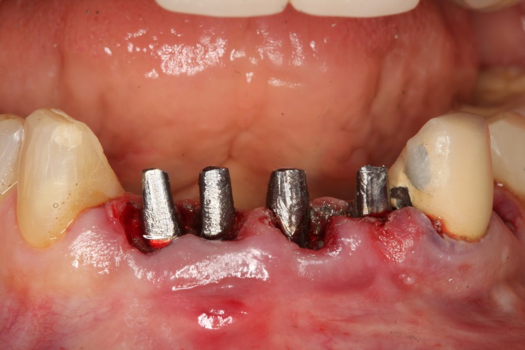

Fig 37. Pontic removal of No. 23 and teeth extractions.

Figure 37

Fig 38. Periodontal casualties.

Figure 38

Fig 39. Surgical guide in place.

Figure 39

On the day of surgery, the plan was to extract teeth Nos. 21, 23, 24, 25, and 26, place 3.0 x 13-mm implants in the anterior region due to limited spacing, and place a 4.1 x 10-mm implant in the No. 21 extraction site. Before the extractions were performed, the No. 23 pontic was sectioned from the existing 2-unit cantilevered bridge utilizing ceramic and metal high speed rotary cutting burs ZR 6881 and H34L (Komet-USA), respectively. After removal of the pontic and extractions, the surgical guide was verified to be seating positively (Figure 36 through Figure 38). Surgical guide protocol was followed, and all implants were successfully placed and torqued to a value of greater than 35 Ncm (Figure 39 and Figure 40). All implants were placed without flapping, with the exception of No. 23. The flap was elevated to reposition lingual keratinized tissue facially for enhanced esthetic tissue profile. The implants were then prepared with a high-speed carbide bur (Komet-USA) with copious amounts of water (Figure 41 and Figure 42). The one-piece 3.0-mm diameter implant served the needs of the patient's spacing requirements. Inter-occlusal space requirements and path of draw were verified. The PMMA provisionals were air abraded and relined with crown-and-bridge material (Figure 43 through Figure 45).